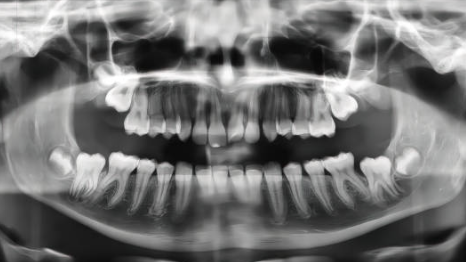

상악동 거상술 임플란트에 대해 알아볼게요. 상악동 거상술은 상악(위턱) 뼈에 임플란트를 식립하기 전에 상악동을 들어 올려 뼈를 이식하는 시술이에요. 상악 부위는 뼈가 얇아 임플란트를 심기 어려운 경우가 많기 때문에, 상악동 거상술을 통해 뼈를 보강해 줄 필요가 있습니다. 오늘은 상악동 거상술 임플란트 시술 과정과 주의사항에 대해 알아볼게요.

상악동 거상술은 위턱 뼈에 임플란트를 식립하기 어려운 경우에 사용돼요. 특히 상악 부위는 뼈가 얇거나 손실된 경우가 많아서 임플란트를 안정적으로 심을 수 없어요.

- 상악 부위의 특성: 상악 부위는 해부학적으로 뼈가 얇고 상악동(비강과 인접한 공간)이 있어요. 임플란트가 상악동에 닿지 않도록 하기 위해 충분한 뼈가 필요해요.

- 뼈 손실: 오랜 시간 치아가 빠진 상태로 방치된 경우, 뼈가 흡수되어 얇아질 수 있어요. 이런 경우 상악동 거상술을 통해 뼈를 추가적으로 이식해야 해요.